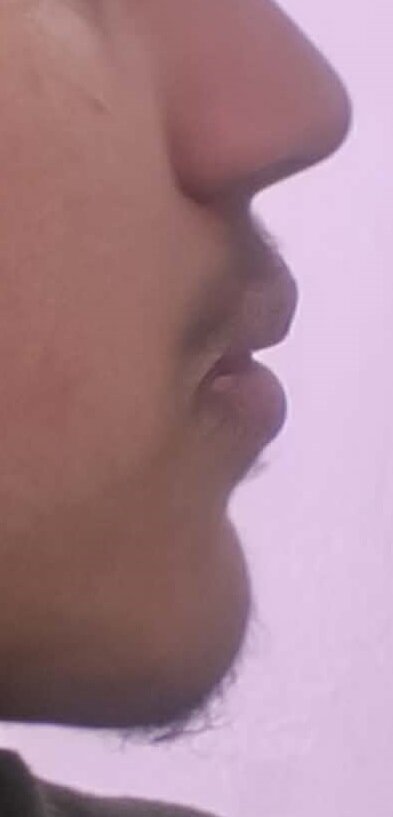

Im going to get damon braces for overbite/overjet and crowding...main thing is that i want my chin to be more forward or the same level as my upper jaw and fix recession,,my teeth are already kind of flared as you can see in picture ,,will damon braces cause them to be more flared and cause my chin to look even smaller compared to lips and upper jaw?